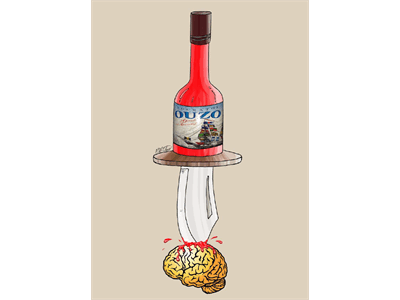

مصرف مشروبات الکلی با تاثیر بر مغز موجب تغییرات رفتاری و خلقی مخرب می شود.